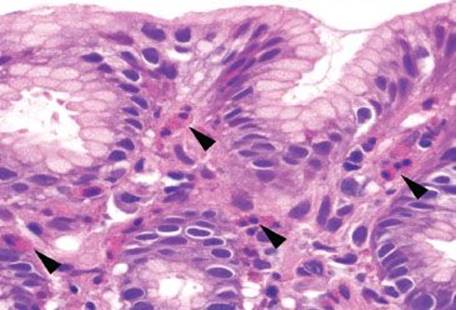

Figure 2.154 Gastric mucosal eosinophilia pattern, peripheral eosinophilia. Higher power of previous case (Fig. 2.153). Numerous eosinophils are present in the lamina propria (arrowheads), with clusters of eosinophils extending to the just below the surface epithelium. The exact etiology of this patient’s diffuse eosinophilic gastroenteritis is unknown.